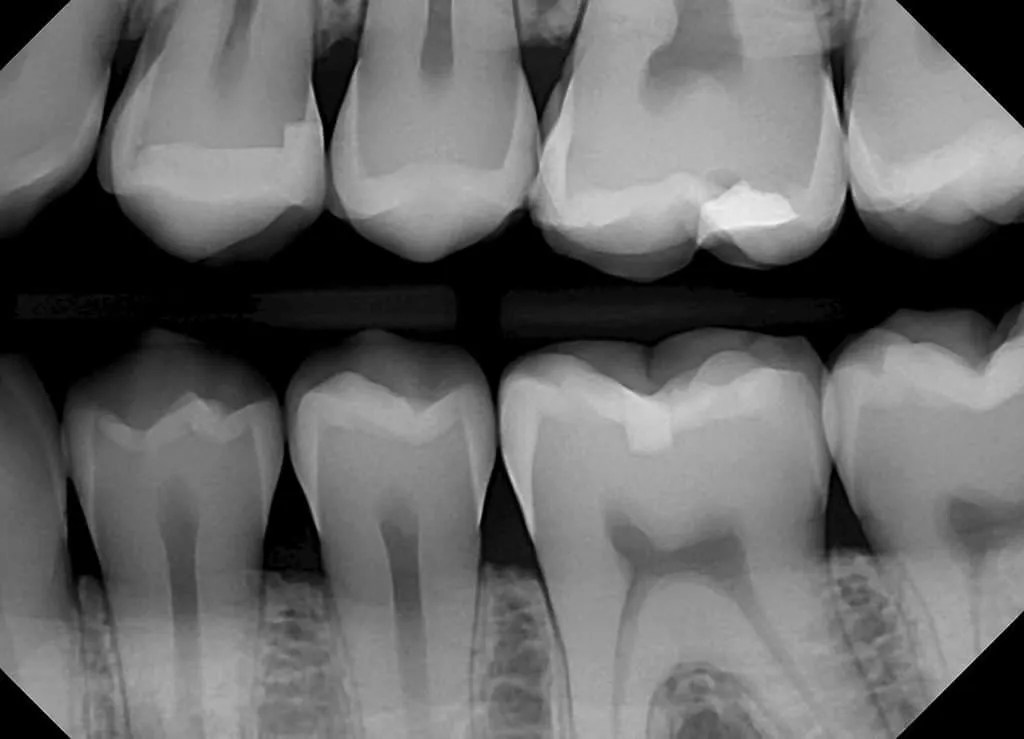

Do X Rays Show Gum Disease . Your dentist may assign a stage and a grade to periodontitis based on how severe the. These images show the areas of bone loss in detail. A history of gum disease (gingivitis) or tooth decay. Inability to remove this plaque with regular brushing and flossing enables plaque to solidify into tartar.